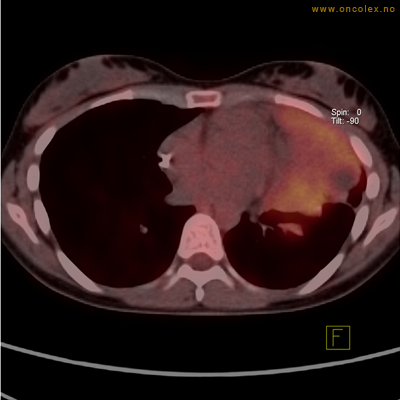

PET/CT (PET: Positron Emisjons Tomografi/ CT: Computer Tomografi) er en avansert nukleærmedisinsk bildetakingsmetode. Metoden er et godt dokumentert, veletablert og svært nyttig verktøy i bildediagnostikk ved kreft. Et PET-kamera gir tredimensjonale bilder av hele kroppen. Integrert CT gjør at informasjonen fra PET blir lokalisert anatomisk nøyaktig.

Kort beskrivelse av undersøkelsen

Gjennom en nål (plastkanyle) i en blodåre i armen vil du få et radioaktivt stoff. Det mest vanlige er radioaktivt druesukker (18F-FDG). Stråling fra det radioaktive stoffet registreres i PET-skanneren og viser hvordan dette stoffet fordeler seg i kroppen. Det normale opptaket av det radioaktive stoffet vil være endret ved sykdomsprosesser. Celler med høyt stoffskite, som for eksempel kreftceller, har økt opptak av sukker. Ved undersøkelsen kan man dermed ofte se større opptak av det radioaktive sporstoffet i kreftsvulster.  Siden CT tas samtidig, kan PET og CT bildene legges sammen og vise nøyaktig hvor i kroppen det økte opptaket er.

Eksempler på funn

Vev som tar opp mer radioaktivt stoff, synes som hvite områder som lyser opp mer i forhold til annet vev som tar opp mindre sukker.